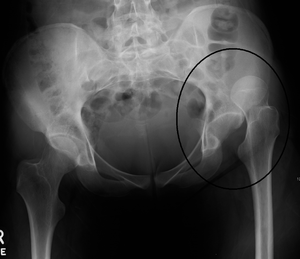

X-ray showing a joint dislocation of the left hip.

Dislocation of the hip is a common injury to the hip joint. Dislocation occurs when the ballshaped head of the femur comes out of the cupshaped acetabulum set in the pelvis. This may happen to a varying degree. A dislocated hip, much more common in females than in males, is a condition that can either be congenital or acquired.[1] Understanding the epidemiology, anatomy, difference between congenital and acquired, screening, treatments, and rehabilitation are all relevant to the topic.